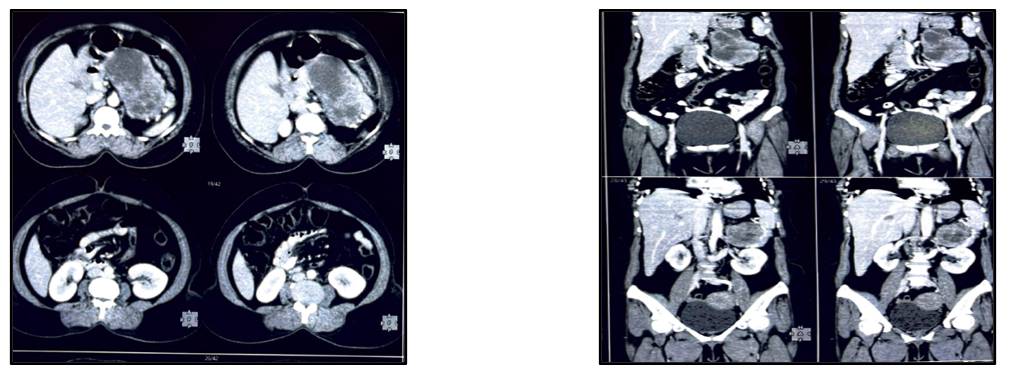

Computerized tomography scan Figure 1. demonstrated large heterogeneously enhancing solid and cystic lesion measuring 12.0x8.0x6.0cms arising from the distal body and tail of pancreas showing coarse central calcifications. It is causing mass effect on the left adrenal gland. Splenic vessels are displaced and coursing along the inferior margin of the lesion. No evidence of pancreatic duct dilation. The lesion shows heterogeneous enhancement of post contrast study -Neoplastic etiology.